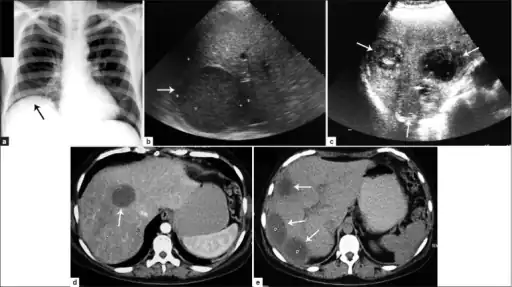

a) Amoebic liver abscess showing the elevation of the right hemi-diaphragm b)single large amoebic abscess and c) three amoebic hepatic abscesses. d) Contrasted computed tomography (CT) scan of a single abscess and e) three clear amoebic liver abscesses -